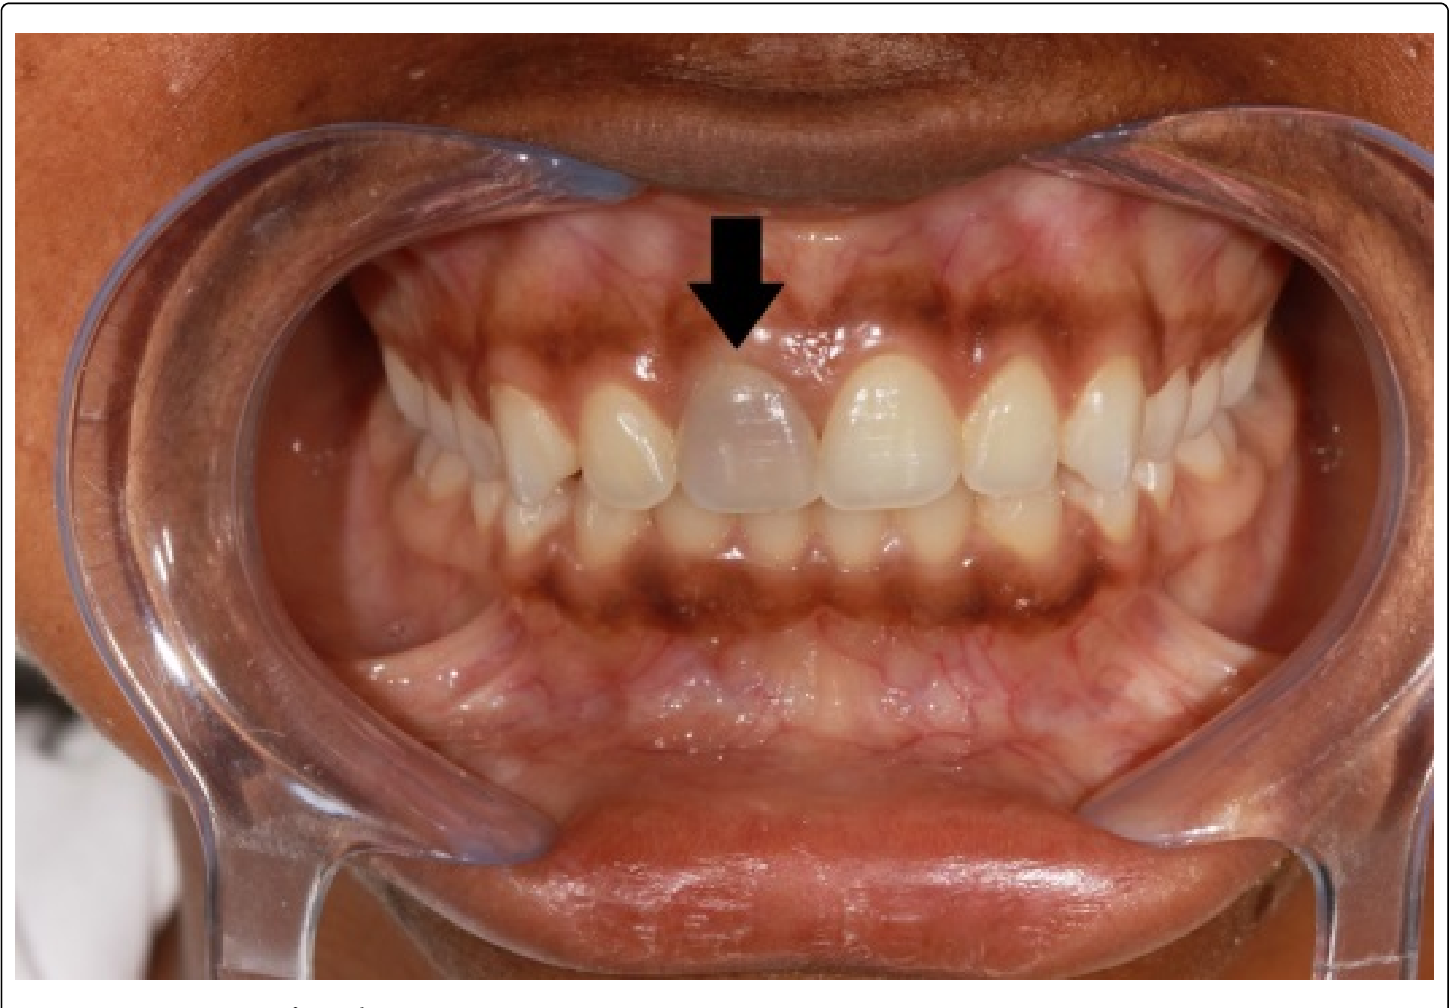

Tooth discoloration

A darkened, grayish, or blackish tooth could indicate pulp necrosis due to a lack of blood supply.